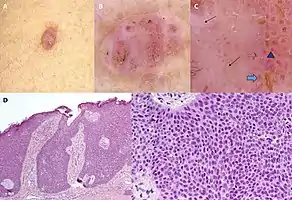

Eccrine clear-cell poroma Dermoscopy and histopathology of eccrine poroma: (A) Clinical presentation of a nonpigmented eccrine poroma sensu stricto as a pink nodule located on the foot (B,C) Dermoscopy shows milky red areas (light blue arrow), milky red globules (dark blue triangle), and dotted vessels (black arrow) (original magnifications ×20 and ×40, respectively). (D,E) Histopathologically, the neoplasm consists of poroid and cuticular cells and tubular structures that are continuous with the epidermis (H&E stain, original magnifications ×10 and ×40, respectively).[6]

Dermoscopy and histopathology of eccrine poroma: (A) Clinical presentation of a nonpigmented eccrine poroma sensu stricto as a pink nodule located on the foot (B,C) Dermoscopy shows milky red areas (light blue arrow), milky red globules (dark blue triangle), and dotted vessels (black arrow) (original magnifications ×20 and ×40, respectively). (D,E) Histopathologically, the neoplasm consists of poroid and cuticular cells and tubular structures that are continuous with the epidermis (H&E stain, original magnifications ×10 and ×40, respectively).[6]